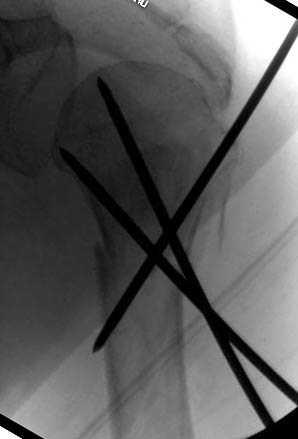

Наличие рентген контроля (ЭОП) помогает во время

репозиции и фиксации, но многие коллеги умудряются без рентгена фиксировать несколькими спицами перкутанно.

Наш недавний случай перкутанной фиксации "методом

Сиэтла" спицами 2.8 мм с резьбой на конце.